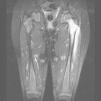

A continuación se presenta el caso de una niña de 5 años que acudió a Urgencias por fiebre e impotencia funcional en miembro inferior izquierdo de 5 días de evolución. Estaba en tratamiento con cefixima por faringoamigdalitis aguda. En la exploración presentaba posición antiálgica, con cadera izquierda en flexión y rotación externa, muslo edematoso, doloroso a la presión, e imposibilidad de movilización de la cadera. El resto de la exploración fue normal. El hemograma, la bioquímica y la coagulación resultaron normales. La proteína C reactiva (PCR) fue de 159,6mg/l. En la ecografía de cadera y muslo se observó aumento de grosor y ecogénesis del vasto lateral del cuádriceps; no se observó derrame articular. Al ingreso, se realizó gammagrafía ósea con Deoxipiridinolina–tecnecio 99 metaestable (DPD–Tc99m) que dio como resultado reacción inflamatoria en el muslo izquierdo e hipercaptación en el tercio proximal del fémur. La niña ingresó con diagnóstico inicial de osteomielitis. Se pautó tratamiento antibiótico intravenoso con cloxacilina y cefotaxima, y tratamiento antiinflamatorio con ibuprofeno oral. Ante la posibilidad de piomiositis asociada a osteomielitis femoral, se realizó gammagrafía con galio (fig. 1) y se evidenciaron 2 focos de captación: uno en la cabeza y el cuello de fémur, y otro en el vasto lateral del cuádriceps. La ecografía de control al alta mostró lesión hipoecogénica en el vasto lateral compatible con absceso muscular. Se realizó una RM (fig. 2), en la que se observó afectación difusa de cabeza y cuello de fémur izquierdo, y otra lesión hiperintensa de 10 × 1cm en el vasto lateral. La niña evolucionó favorablemente con el tratamiento médico y no precisó abordaje quirúrgico. La fiebre se suspendió al cuarto día del ingreso, con mejoría progresiva de la movilidad activa y pasiva de la cadera, y desaparición de la tumefacción en el muslo. La deambulación al alta era normal. El hemocultivo fue estéril y no se realizó cultivo del músculo ni del hueso. El tratamiento antibiótico intravenoso se mantuvo hasta completar 21 días y al alta se pautó amoxicilina con ácido clavulánico por vía oral.

Para mejorar el pronóstico y evitar que la enfermedad alcance la tercera fase, es importante un diagnóstico precoz y un tratamiento adecuado. Las pruebas de imagen son fundamentales1,4; la más conveniente es la RM, que proporciona información acerca de la afectación local y del tamaño. La gammagrafía con galio es útil a la hora de encontrar otros focos, ya que la piomiositis puede ser multifocal hasta en un 40% de los casos3. Del 5 al 40% de las veces, el hemocultivo es positivo y la conveniencia del cultivo del exudado recogido por punción o drenaje alcanza porcentajes cercanos a la totalidad de los casos1. Otras pruebas útiles son la ecografía (que debe realizarse en primer lugar debido a su seguridad, accesibilidad y bajo coste), la radiografía y la gammagrafía con DPD-Tc99m para detectar una posible afectación ósea.